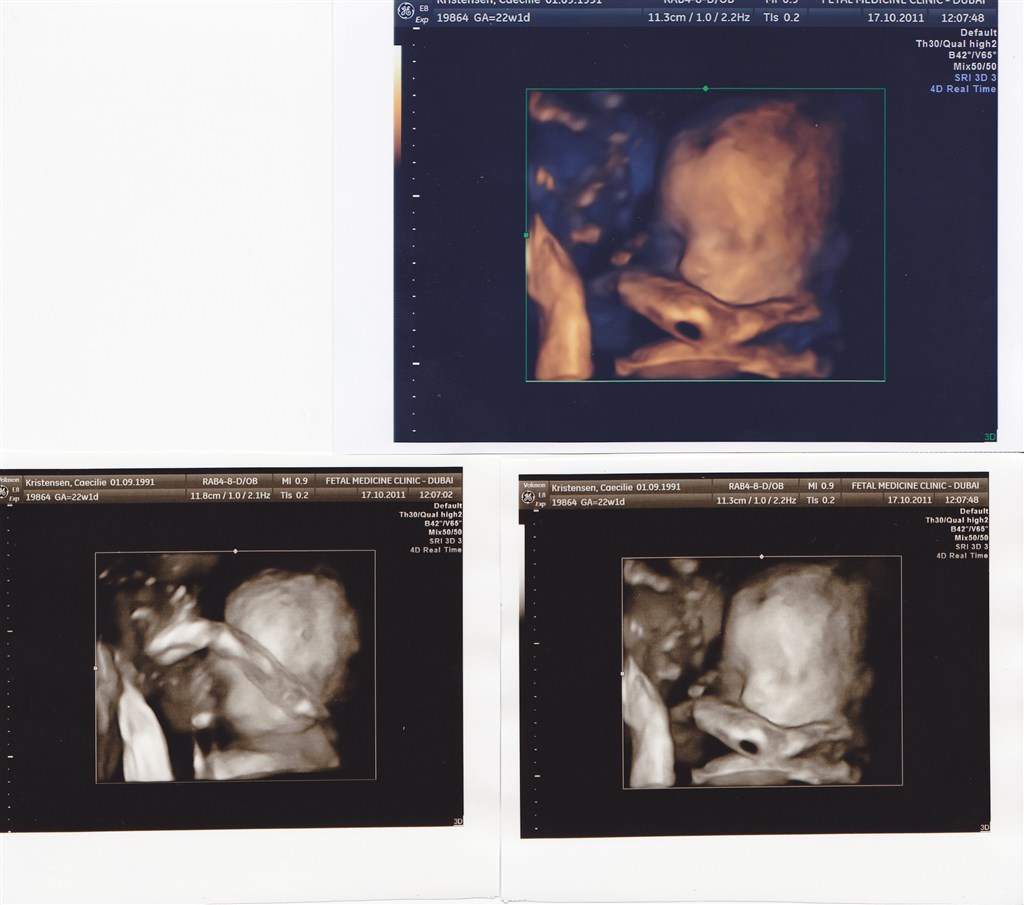

Her er lige et par billeder fra min MD-scanning i dag. Perfekt lille pige på 418 g. og 35 (!!!!) cm. Lange asen

Alt er som det skal være - hun ligger på gennemsnittet i alle skalaer, så det er jo bare dejligt!

Nå, men her er lige et par billeder. Hun er lidt sky og drillede da vi skulle have taget billeder. Men synes nu de er gode alligevel